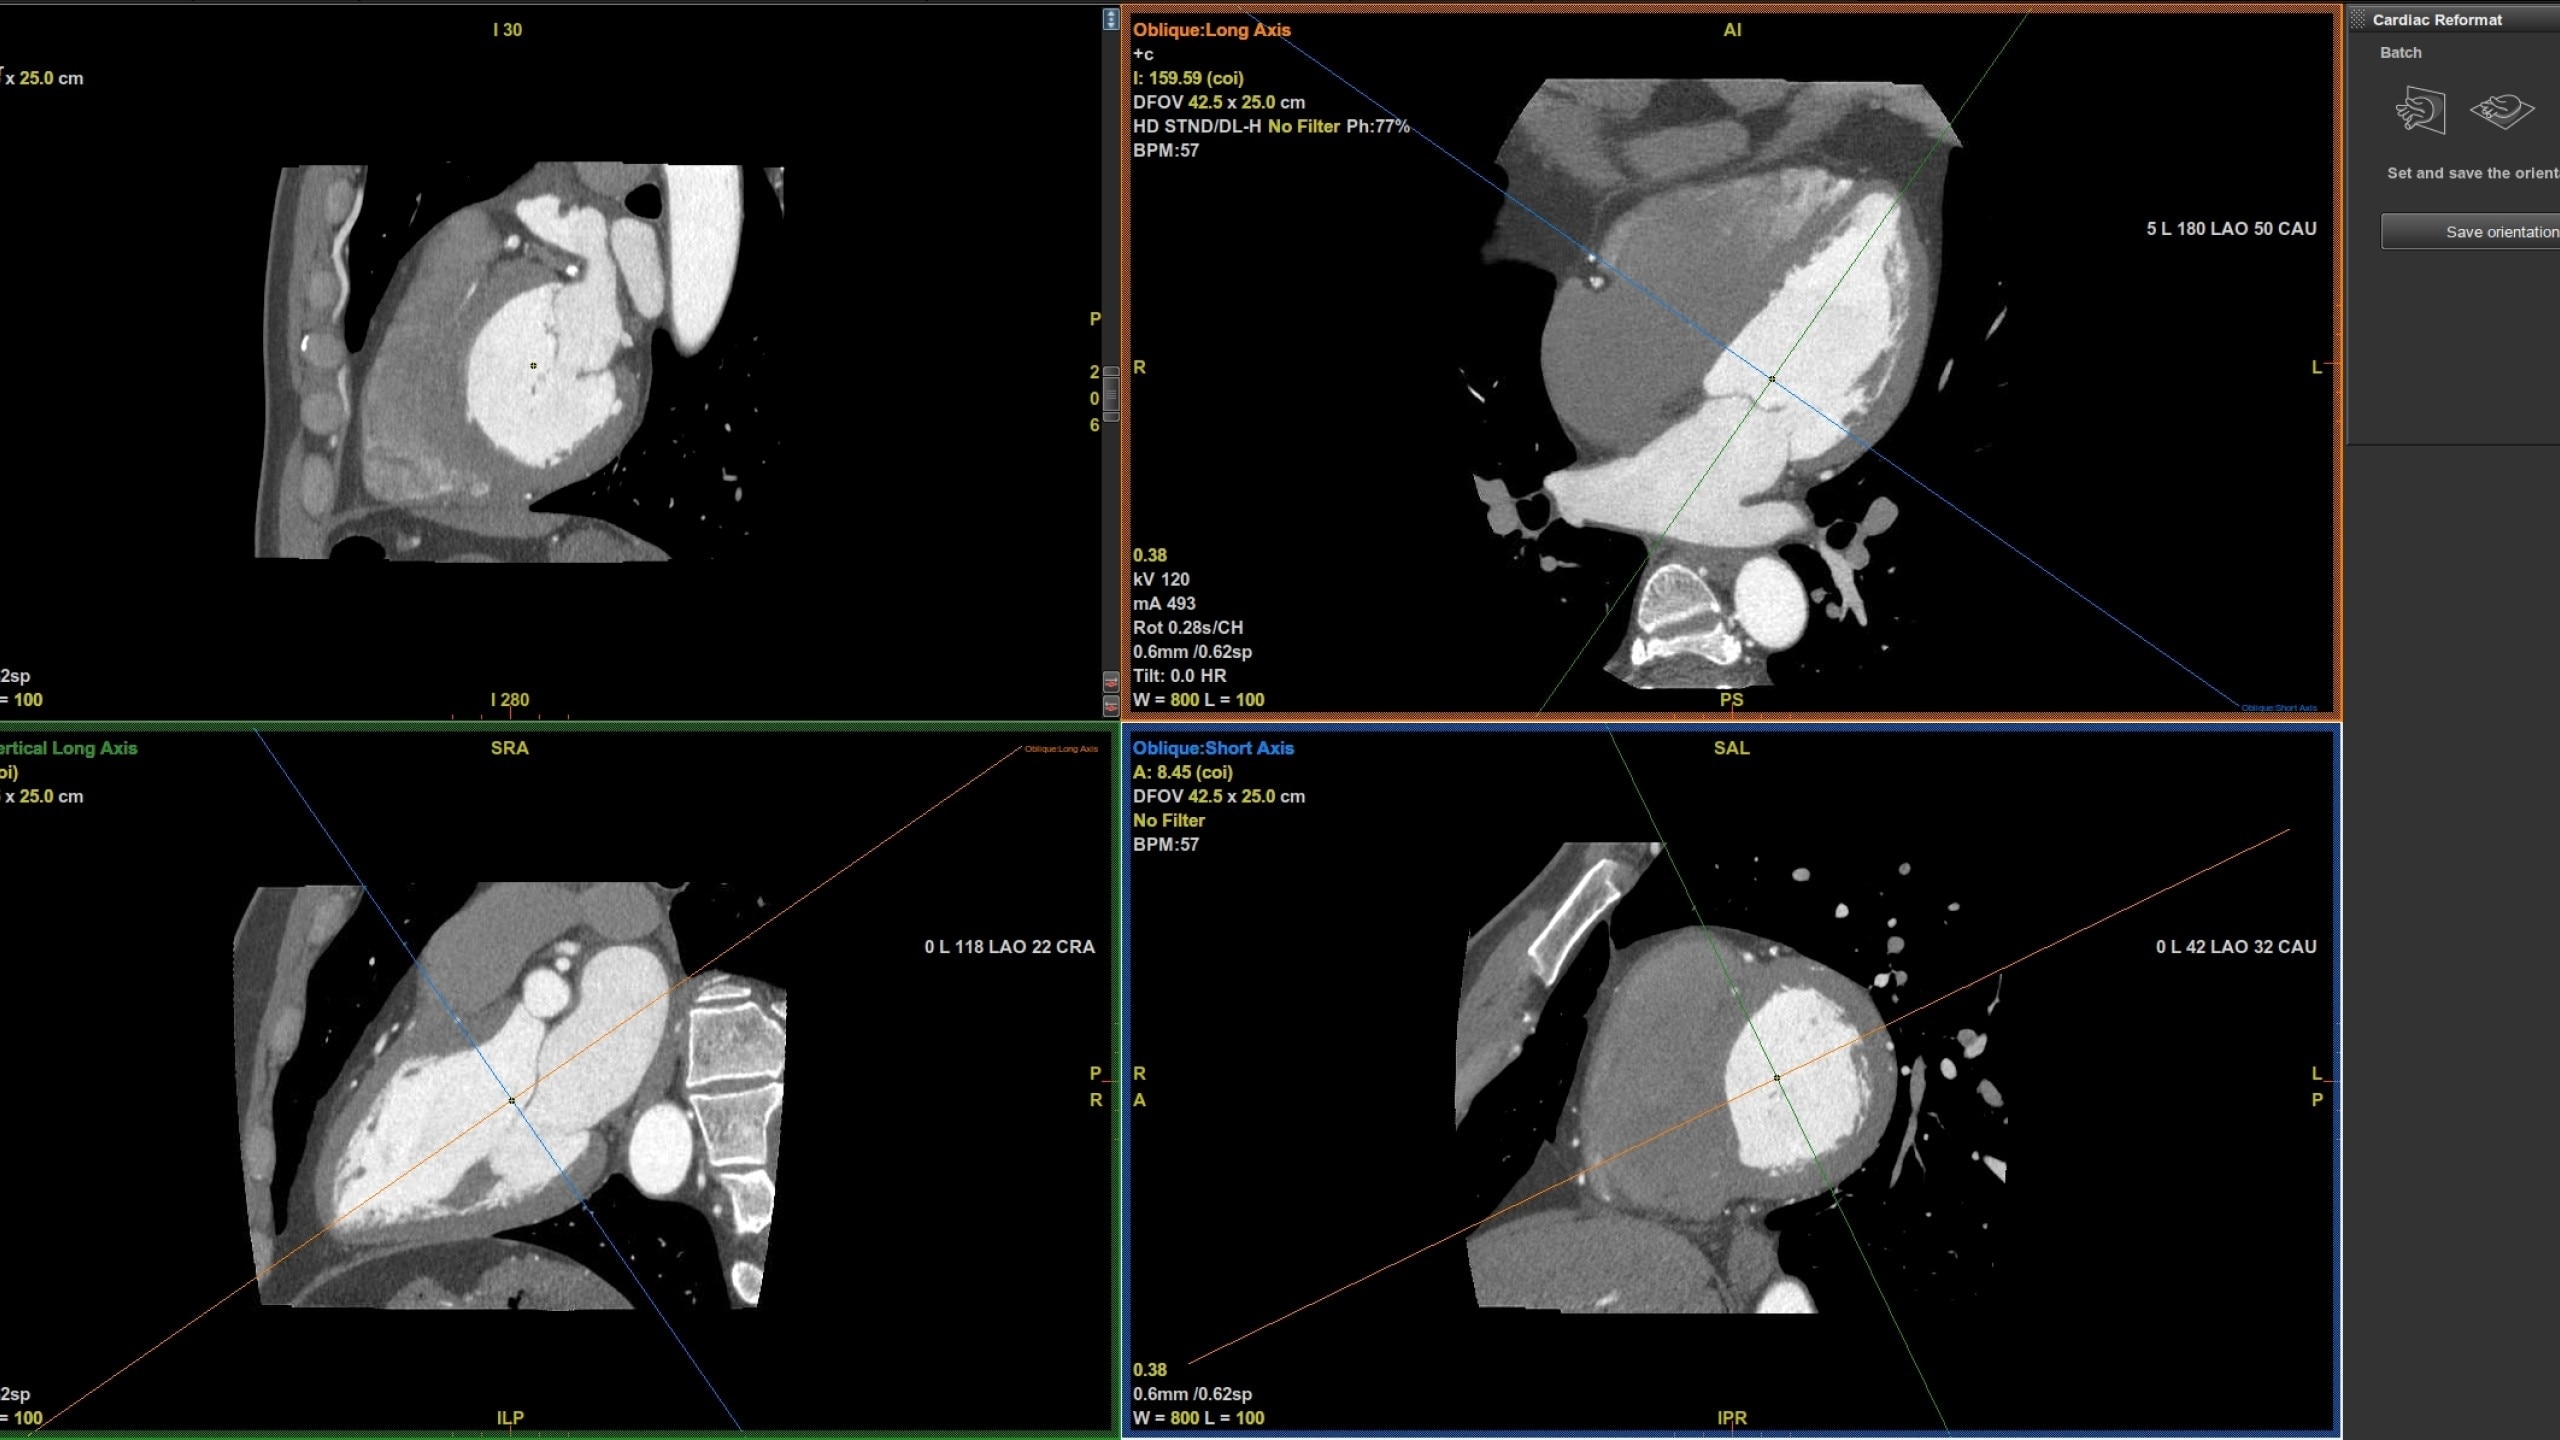

• Pre-processing automatically recognizes cardiac

datasets and performs all segmentations as data

arrives on the system saving processing time

• Auto Coronary analysis automatically segments the

coronary tree, tracks and labels the coronary arteries

• Three pre-defined orientation protocols for easy review

of the coronary vessels and chambers